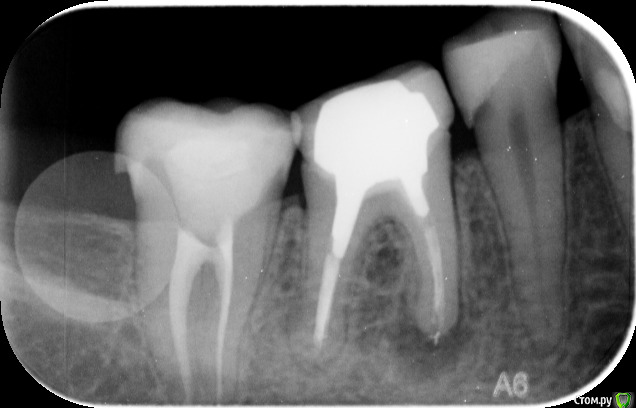

Сашуля Опубликовано 8 декабря, 2016 Поделиться Опубликовано 8 декабря, 2016 (изменено) Здравствуйте уважаемые стоматологи.Очень хочется получить совет.Имею хронический периодонтит. Температура 37,3 постоянно, впрочем, это мне не мешает.Первое фото. Когда обнаружили периодонтит. 2013 год.Второе фото-в процессе лечения.Мне запломбировали каналы, постави вкладку, налили пластиковую временную коронку и отправили в свободное плавание. Зуб никак не беспокоил.Наблюдалась, делала снимки с определённой периодичностью. Зуб не беспокоил.Сейчас настал решающий момент. Последние два снимка были сделаны сегодня. Сторона с проблемным зубом ноет, непонятно, что это болит, толи соседние зубы, толи периодонтит беспокоит. Боль усиливается к вечеру. При надавливании на проблемный зуб острая боль. При внешнем осмотре всё в норме.Вообще грозятся удалять или сделать Гемисекцию. Чего мне ожидать, может быть можно по данным снимкам чтото выяснить.Спасибо. Изменено 8 декабря, 2016 пользователем Сашуля Ссылка на комментарий

DmitrySH Опубликовано 8 декабря, 2016 Поделиться Опубликовано 8 декабря, 2016 Последний снимок не четкий. Видимо нужна ревизия каналов. Еще 5тый зуб, кариес под пломбой 1 Ссылка на комментарий

IvanK Опубликовано 8 декабря, 2016 Поделиться Опубликовано 8 декабря, 2016 Последний снимок выглядит не плохо, я бы сделал кт скорее всего у Вас пульпит 5го Боль усиливается к вечеру. 1 Ссылка на комментарий